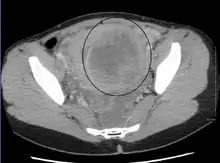

Uterine fibroids as seen during laparoscopic surgery